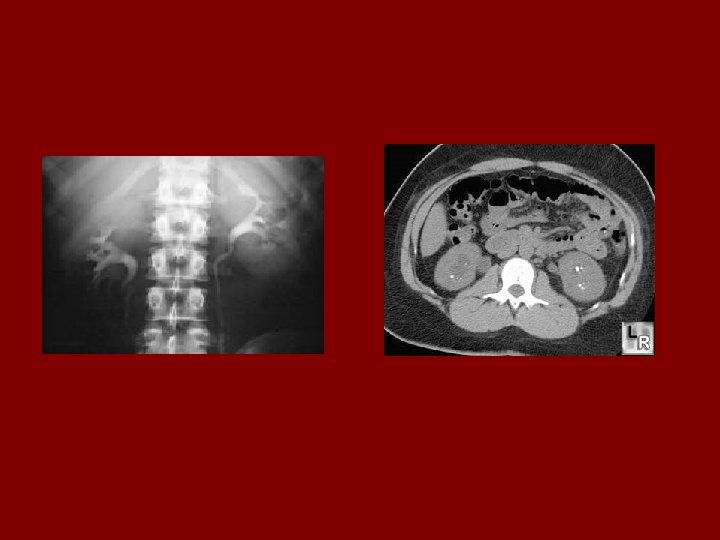

AUTOSOMAL DOMINANT POLYCYSTIC KIDNEY DISEASE • Prevalence: 1: 300 to 1: 1000 • 90% of cases are inherited, 10% are sporadic • Only 1 to 5% nephrons developed cysts • Cysts are in medulla and cortex • ADPKD causes symptoms in third or fourth decade • 50% of patients developing ESRD by age 60

Diagnostic Criteria- Ultrasound • Age 15 -29 ………. . 2 cysts in one or both kidneys • Age 30 to 59 ……. 2 cysts in each kidney • Age >60 …………. 4 cysts in each kidney